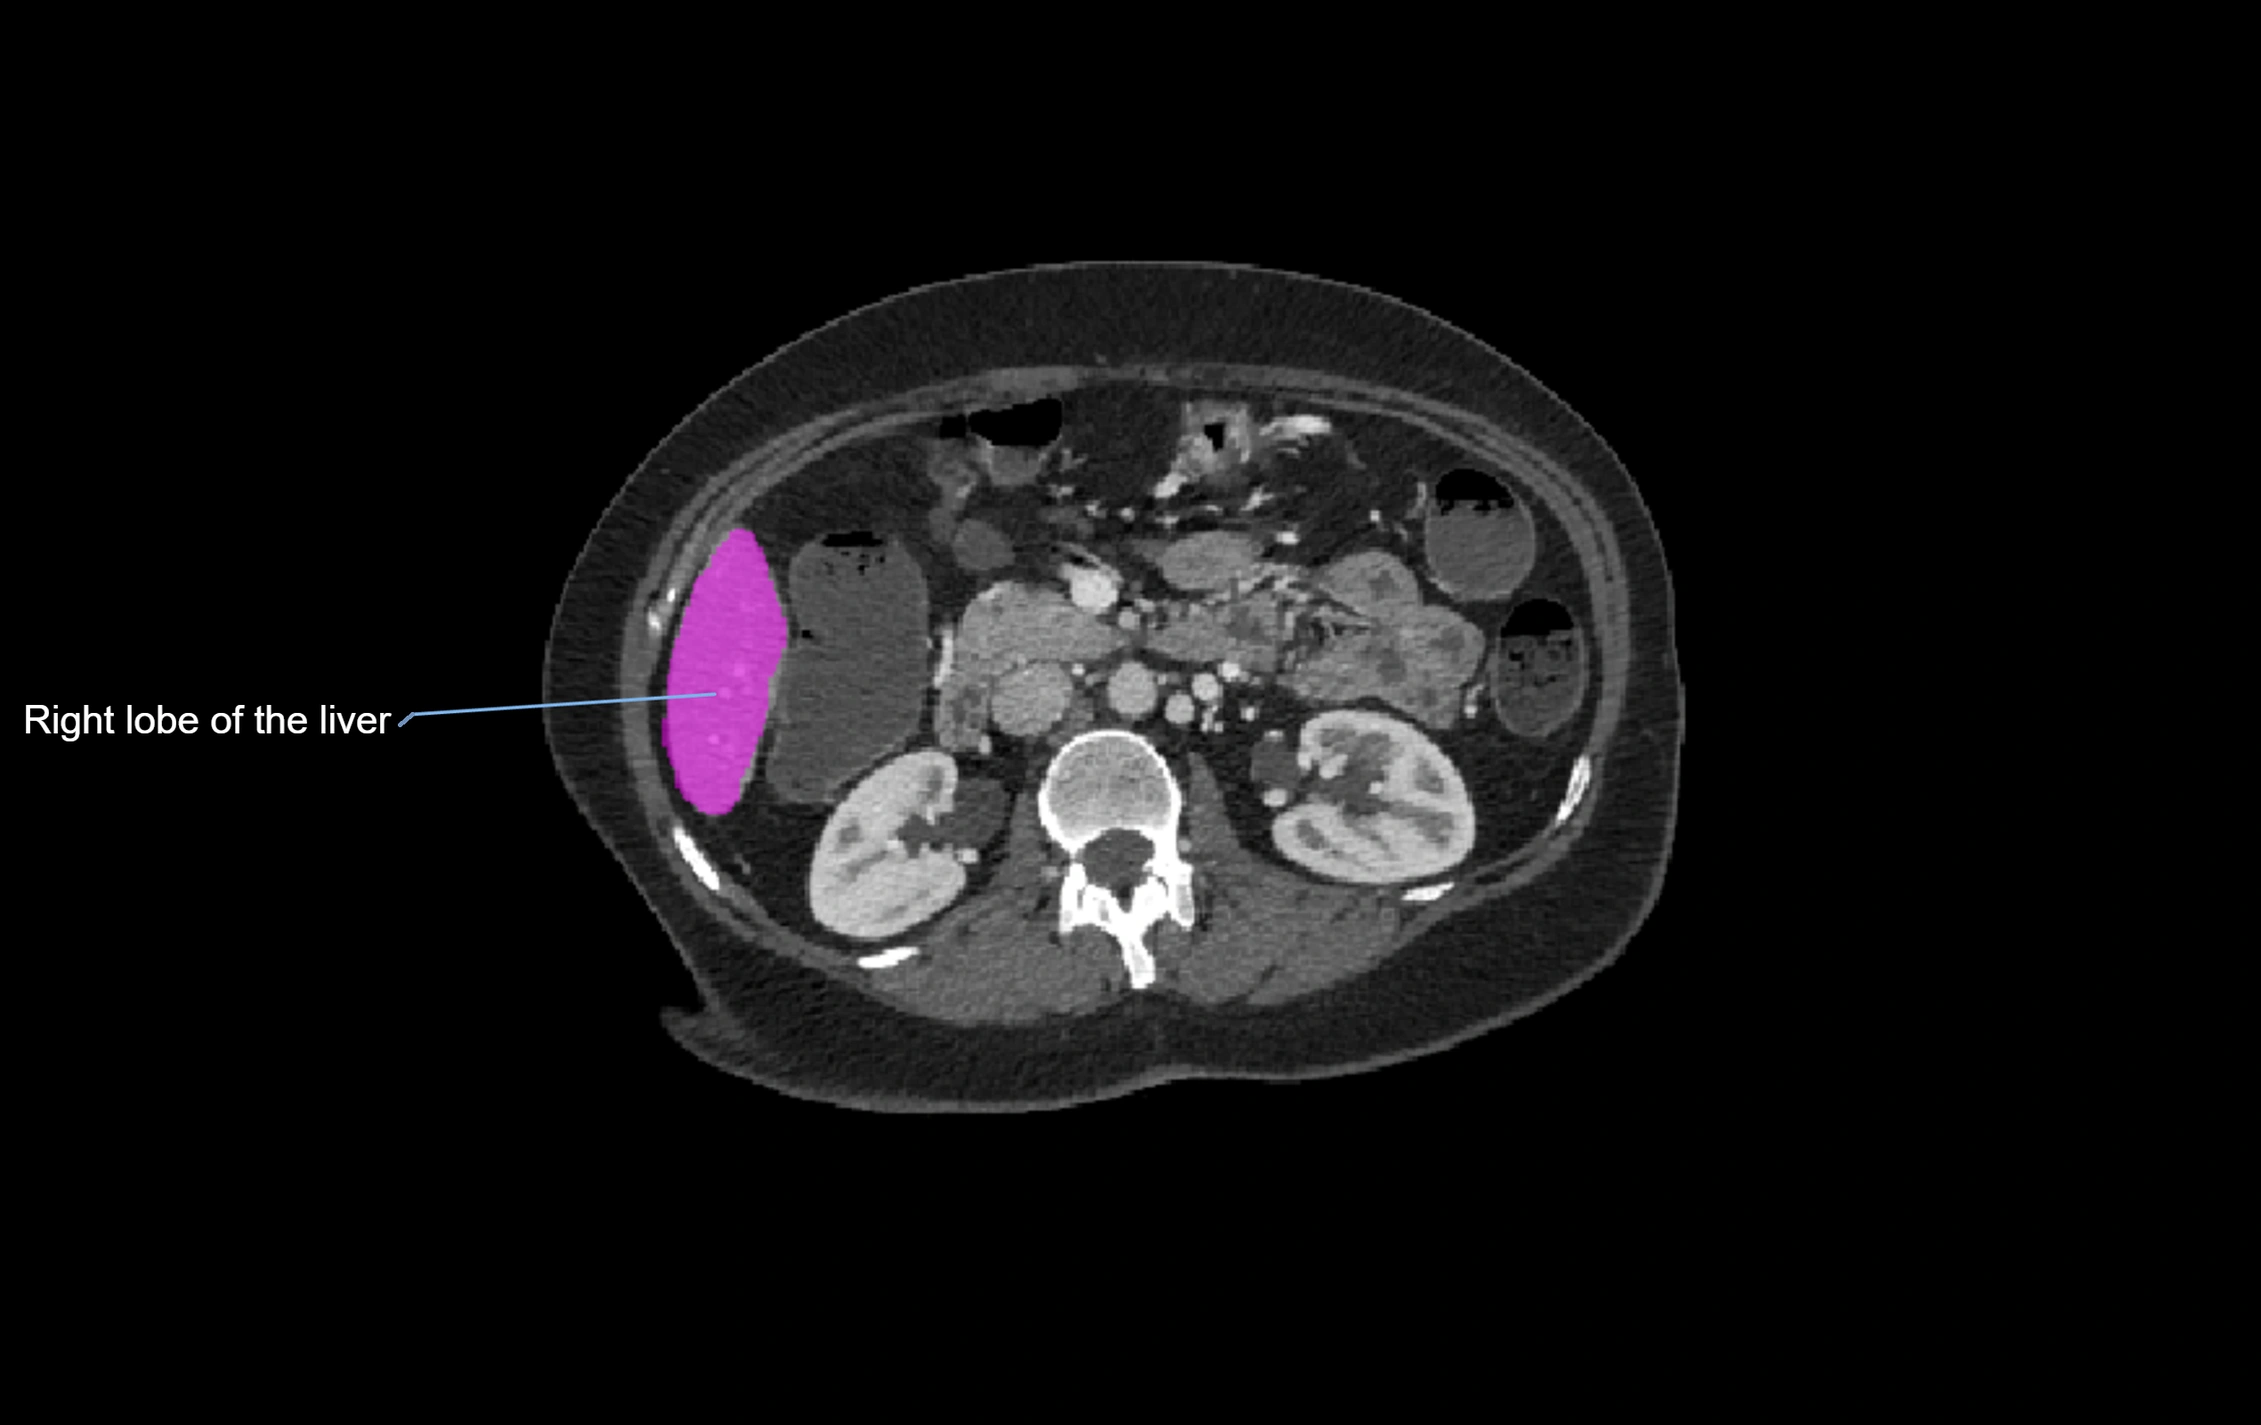

CT Appearance

CT Pre-Contrast:

• Caudate lobe appears as a soft-tissue density, isodense to the rest of the liver

• Enlargement may be appreciated in cirrhosis or Budd–Chiari syndrome

CT Post-Contrast:

• Homogeneous enhancement in the portal venous phase, similar to rest of liver

• Independent venous drainage into the IVC may be visualized

CT Image

image